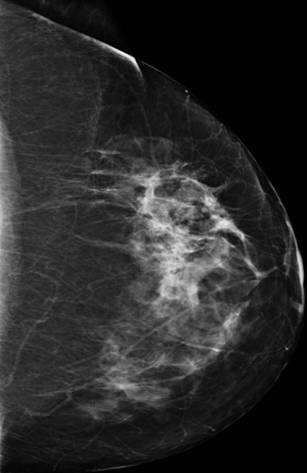

Ung thư vú

» Thông tin: Nữ giới – 58 tuổi.

» Lâm sàng: Khối tuyến vú.